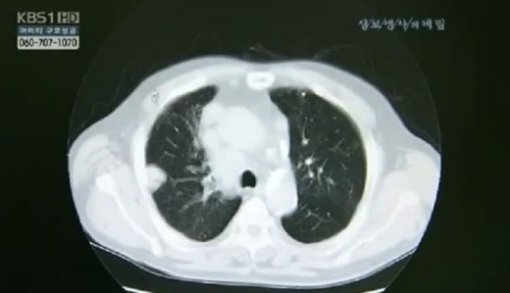

한국인 폐암 유형 1위 ‘선암’을 재발시키는 유전자가 발견돼 학계의 관심이 높다.

서울아산병원 암병원 폐암센터 장세진, 김형렬 교수팀은 지난 13일 한양대의대, 서울대 자연과학대 연구팀과 공동으로 폐절제술을 받은 폐선암 환자 247명을 대상으로 유전체를 분석, 연구했다.

실험 결과에 따르면 RB 유전자의 돌연변이가 한국인 폐암 유형 1위로 수술 후 조기 폐암의 재발에 영향을 미치는 것으로 나타났다.

연구결과 RB 유전자에 돌연변이를 가진 환자가 폐암의 재발없이 지낼 확률은 20%로, RB 유전자에 변이가 없는 환자의 60%보다 훨씬 낮은 수치다.

폐암은 국내 사망률 1위의 암으로 최근에는 폐의 선(腺)세포에 생기는 ‘선암’ 발병률이 국내 폐암 환자 중 40%에 달한다.

조기 폐선암의 경우 1기라 할지라도 10~20%는 수술 후 재발하기 때문이다.

지금까지 폐선암 재발을 예측할 수 있는 특정 바이오마커는 규명되지 않고 있었다. 이번 한국인 폐암 유형 1위 돌연변이 유전자의 발견으로 폐선암 재발 예측과 표적 약물치료 등 폐선암의 맞춤형 치료에 한발 더 다가설 수 있을 것으로 보인다.